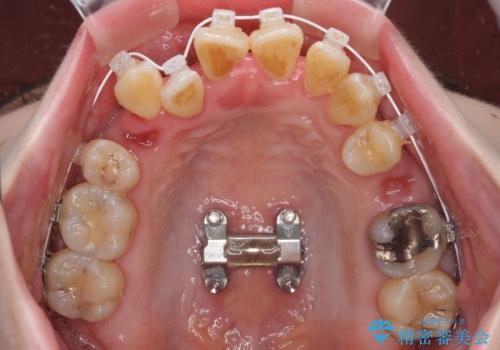

急速拡大装置 狭い骨幅を拡大した上で、顕著なデコボコを改善する抜歯矯正治療

上顎骨よりも下顎骨の幅が広く、更には下顎骨が左側に変位していたため、より良い咬み合わせを達成することを目的として、急速拡大装置を用いて上顎骨を拡大することとしました。

デコボコが強い上に、口元の突出感も気にしていたため、上下左右の小臼歯4本を抜歯して、ワイヤー装置にて矯正治療を行うこととしました。

歯根露出が顕著であったため、歯の移動は早く、スムーズに治療を終えられるかと思いましたが、歯槽骨が硬く、治療は長期間に及びました。

過剰に力をかけ続ける事態となり、一部の歯では変色したり、神経が失活したりとトラブルが続きました。

それでも当初とは比べものにならないほど、綺麗な歯列に仕上げることができました。